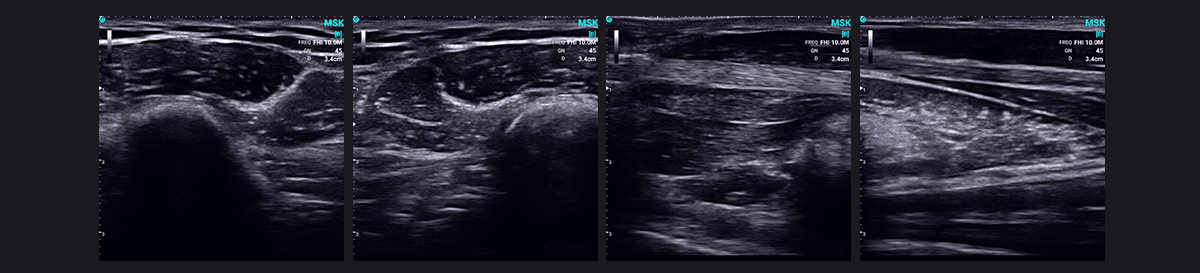

肌肉骨骼超声与 SonoEye:彻底改变诊断成像

肌肉骨骼超声(MSK)近年来已成为一项突破性技术,利用高频超声来诊断肌肉骨骼系统疾病。它提供肌肉、肌腱、韧带、周围神经和其他浅表软组织结构的清晰图像,识别炎症、肿瘤、损伤和畸形等状况。

MSK 超声波在诊断关节疾病方面特别有效,包括类风湿性关节炎和痛风性关节炎。它还有助于检测代谢和全身疾病以及相关的关节。峁└髦植≈⒌娜媸油。

此外,超声波的实时动态成像功能可以检测和观察仅在运动期间或特定位置出现的异常或病变,例如肌腱和神经脱位或肩部撞击综合症。它还可以同时扫描受影响的一侧和健康的一侧,从而有助于动态比较组织结构以识别异常情况。